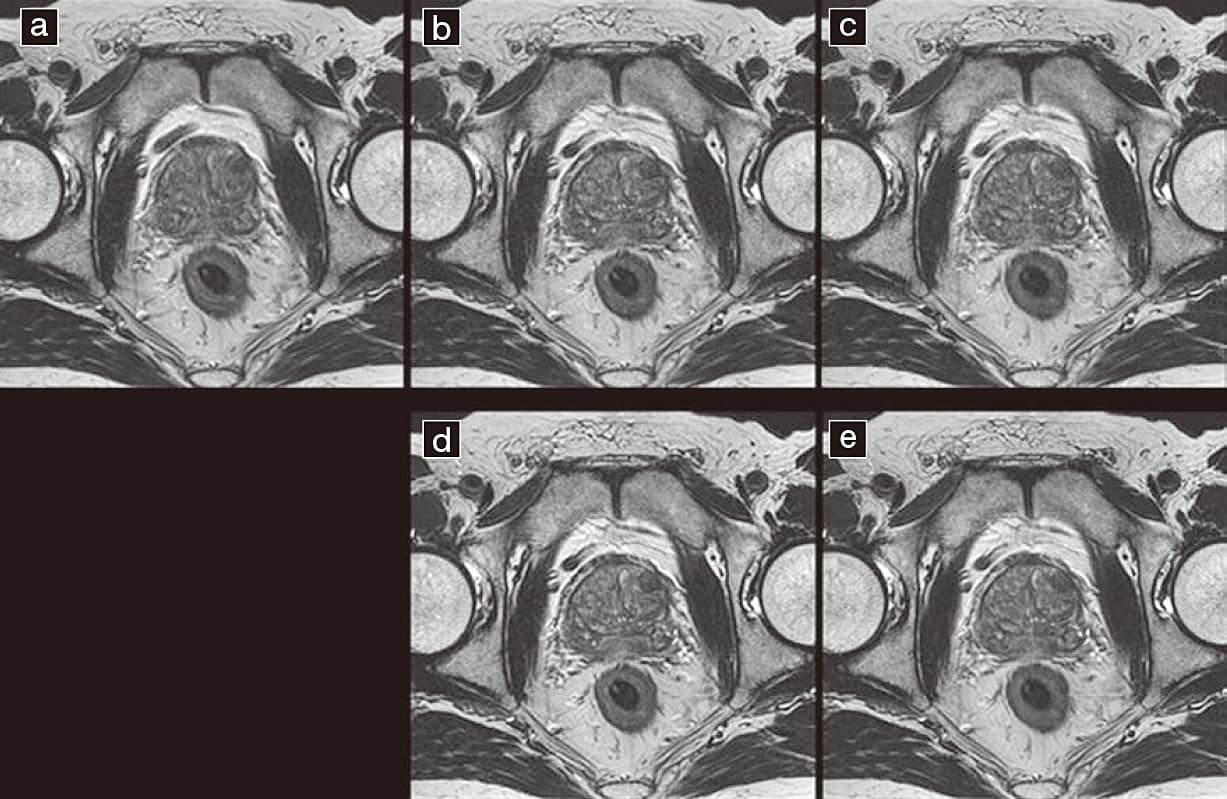

また前立腺においては、近年PI-RADSが提唱されカテゴリを決定するうえでT2強調画像、DWI、ダイナミックスタディが重要視されている。中でもT2強調画像による分解能とSNRを維持された、辺縁領域、移行域領域など解剖学的構造の把握とDWI(ADC)での診断が重要となる。Compressed SPEEDERとAiCEを用いることで高速化と高画質を両立することができた(図10)。

図10 AiCE画像

図10 前立腺 T2 強調画像 高速化・高解像度画像

a:T2強調画像(FSE 2D) SPEEDR1.0 iReso0.4×0.4scan time2:43s

b:T2強調画像(FSE 2D) SPEEDR1.8 iReso0.4×0.4scan time1:51s

c:T2強調画像(FSE 2D) SPEEDR1.3 iReso0.3×0.3scan time2:43s

d:T2強調画像(FSE 2D) SPEEDR1.8 iReso0.4×0.4scan time1:51s AiCE

e:T2強調画像(FSE 2D) SPEEDR1.8 iReso0.3×0.3scan time2:43s AiCE

高解像度化やparallel imagingによる高速化を図るとSNRの低下を及ぼす。 AiCE処理により高速化、高解像度化でSNRの低下を改善できた。